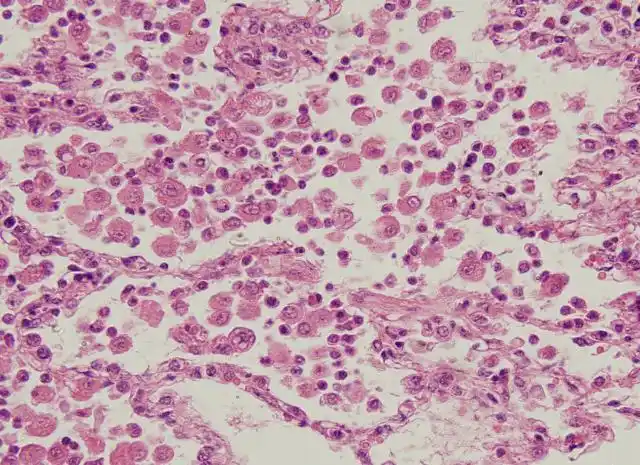

炎性细胞

病理学吞噬作用炎症介质及炎细胞